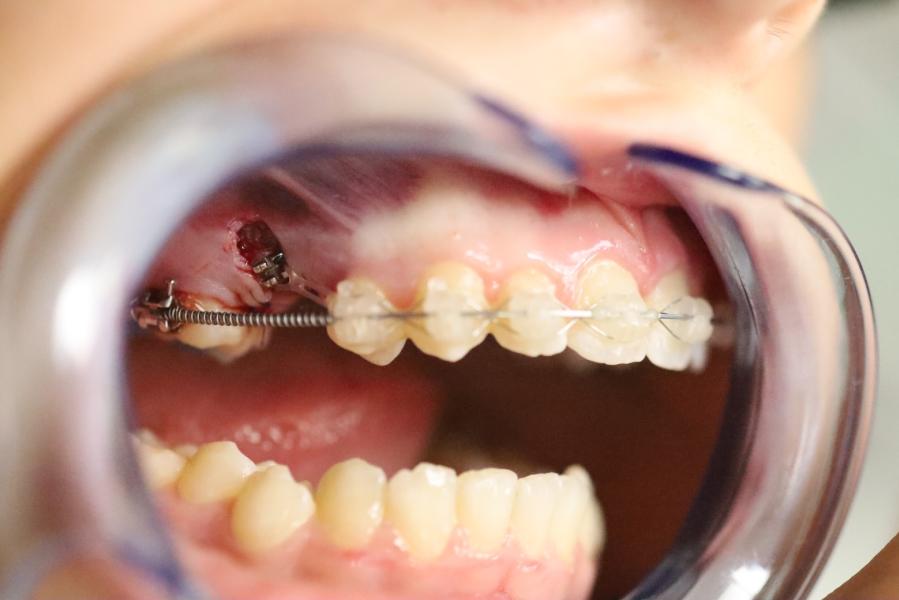

Удалили молочный зуб. Поставили брекеты для того, чтобы создать избыток места для зачатка постоянного зуба и ждали. Очень хотели, чтобы зачаток долгожданного зуба прорезался сам. Но спустя 6 месяцев ничего не произошло, зуб сам прорезаться не стал. И под контролем рентгена мы приняли решение сделать хирургический доступ к этому зачатку. И «насильно» стали тянуть его в нужном нам направлении.

Сейчас зуб (новый, который тянули) стоит в зубном ряду и функционирует! Ничего не угрожает здоровью соседнего зуба(шестерке). За шестеркой будем наблюдать. Должен прослужить долгие годы.